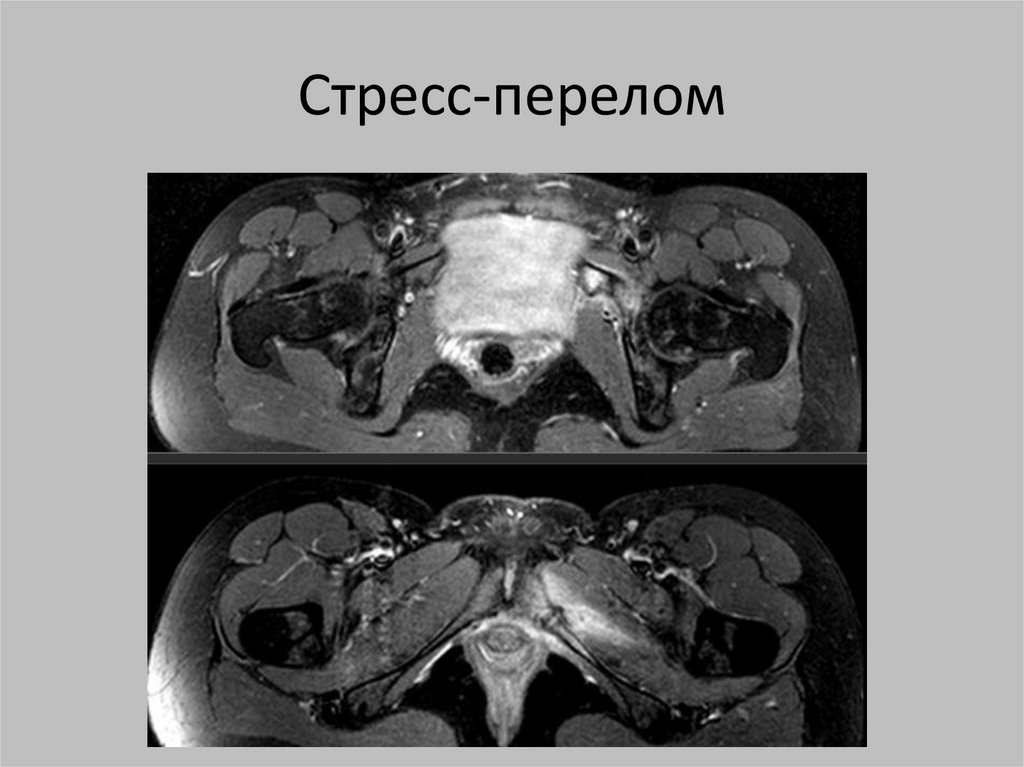

Стресс-перелом

Стресс-переломы